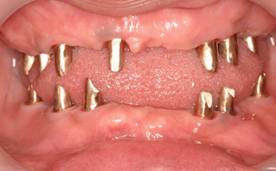

白金加金のアバットメント(土台)

上顎

下顎